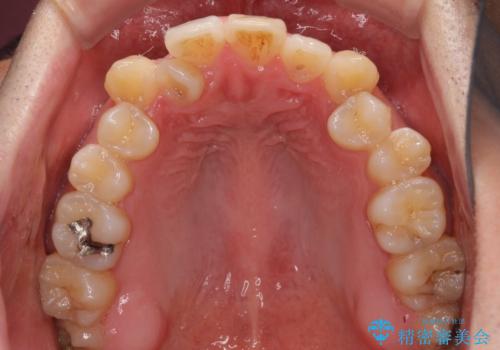

- 八重歯と前歯のデコボコを気にして来院された患者様です。

営業職であり、商談などで飲食をする機会が多いとのことで、インビザラインではなく、ワイヤー装置にて矯正治療を行うこととしました。

舌の突出癖がなかなか改善されず、上下前歯部の接触が得られるまでに予定の倍ほどの期間がかかりました。